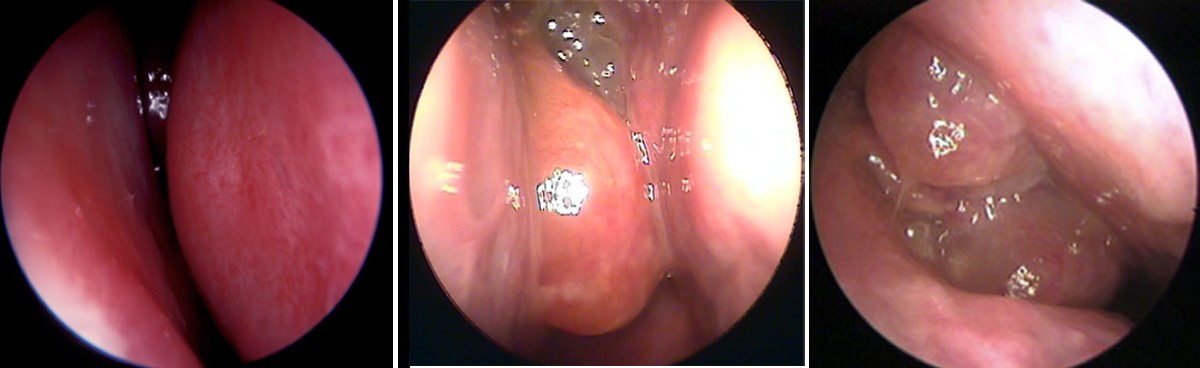

Phù nề niêm mạc mũi gây nghẹt mũi do giãn mạch và sung huyết cuốn mũi

Đặc biệt, cuốn mũi dưới chứa hệ thống xoang tĩnh mạch lớn (venous sinusoids). Khi phản ứng viêm xảy ra, các xoang này giãn ra nhanh chóng, làm đường thở hẹp lại dù dịch không nhiều.

Nghẹt mũi làm tăng áp lực xoang gây đau đầu vùng trán và sau hốc mắt

Rối loạn dẫn lưu xoang và tăng áp lực xoang:

Các xoang cạnh mũi (xoang trán, xoang hàm, xoang sàng, xoang bướm) thông với hốc mũi qua lỗ nhỏ.

Khi niêm mạc phù nề:

-

Lỗ thông bị hẹp

Áp lực trong xoang thay đổi

Dẫn lưu dịch bị hạn chế.

Áp lực âm hoặc dương bất thường trong xoang có thể kích thích thụ thể đau → gây đau vùng: